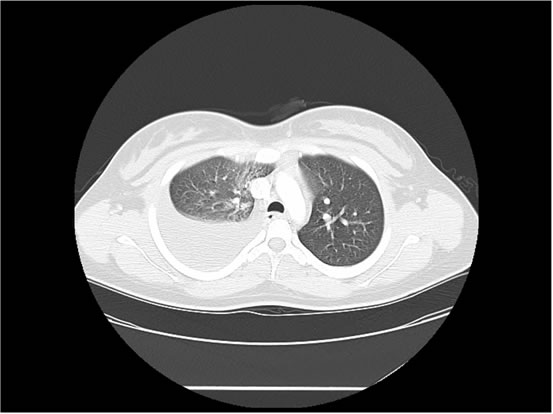

We ordered a CT scan with infusion of the chest

I will show you 12 CT-scan cuts.